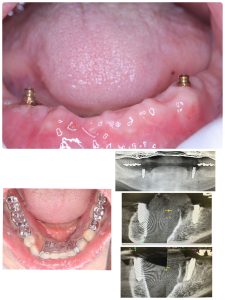

最善の策は、インプラント併用のI.O.Dインプラントオーバーデンチャーがベスト、沈み込み無し、義歯が動かないから良く噛める!

粘膜厚み1から2ミリと薄い方で、痛み出易い方には最適!

画像は87歳の社長だか会長さんは、何でも噛めると元気満々😃